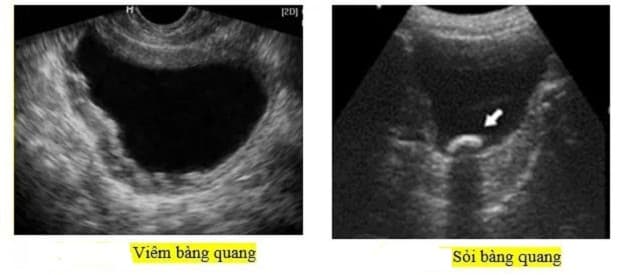

Từ hình ảnh siêu âm có thể đánh giá được thể tích của bàng quang (thể tích nước tiểu tồn lại sau khi đi tiểu, nghi ngờ bí tiểu do tắc nghẽn ở cổ bàng quang), sỏi bàng quang và một số bất thường khác như tình trạng dày thành, các tổn thương polyp, u và túi thừa bàng quang.

Hình ảnh viên sỏi khi được quan sát bằng phương pháp siêu âm sỏi bàng quang